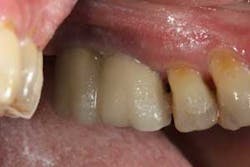

There have been numerous case reports in the literature demonstrating infections of dental implants caused by pathology from the adjacent natural tooth. (1) These infections from adjacent teeth can travel quite quickly to the proximal dental implant (figures 1a and 1b) and cause a rapid degree of bone loss. Treatment can consist of loss of teeth, loss of the dental implants, and/or costly regenerative repair (figure 2). (2) This situation is highly preventable if detected early and endodontic therapy is initiated.